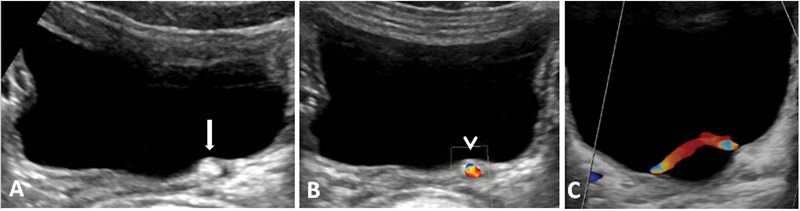

Unraveling the Veil: Deflux Injection Masquerading as Calculus at the Vesicoureteric Junction.